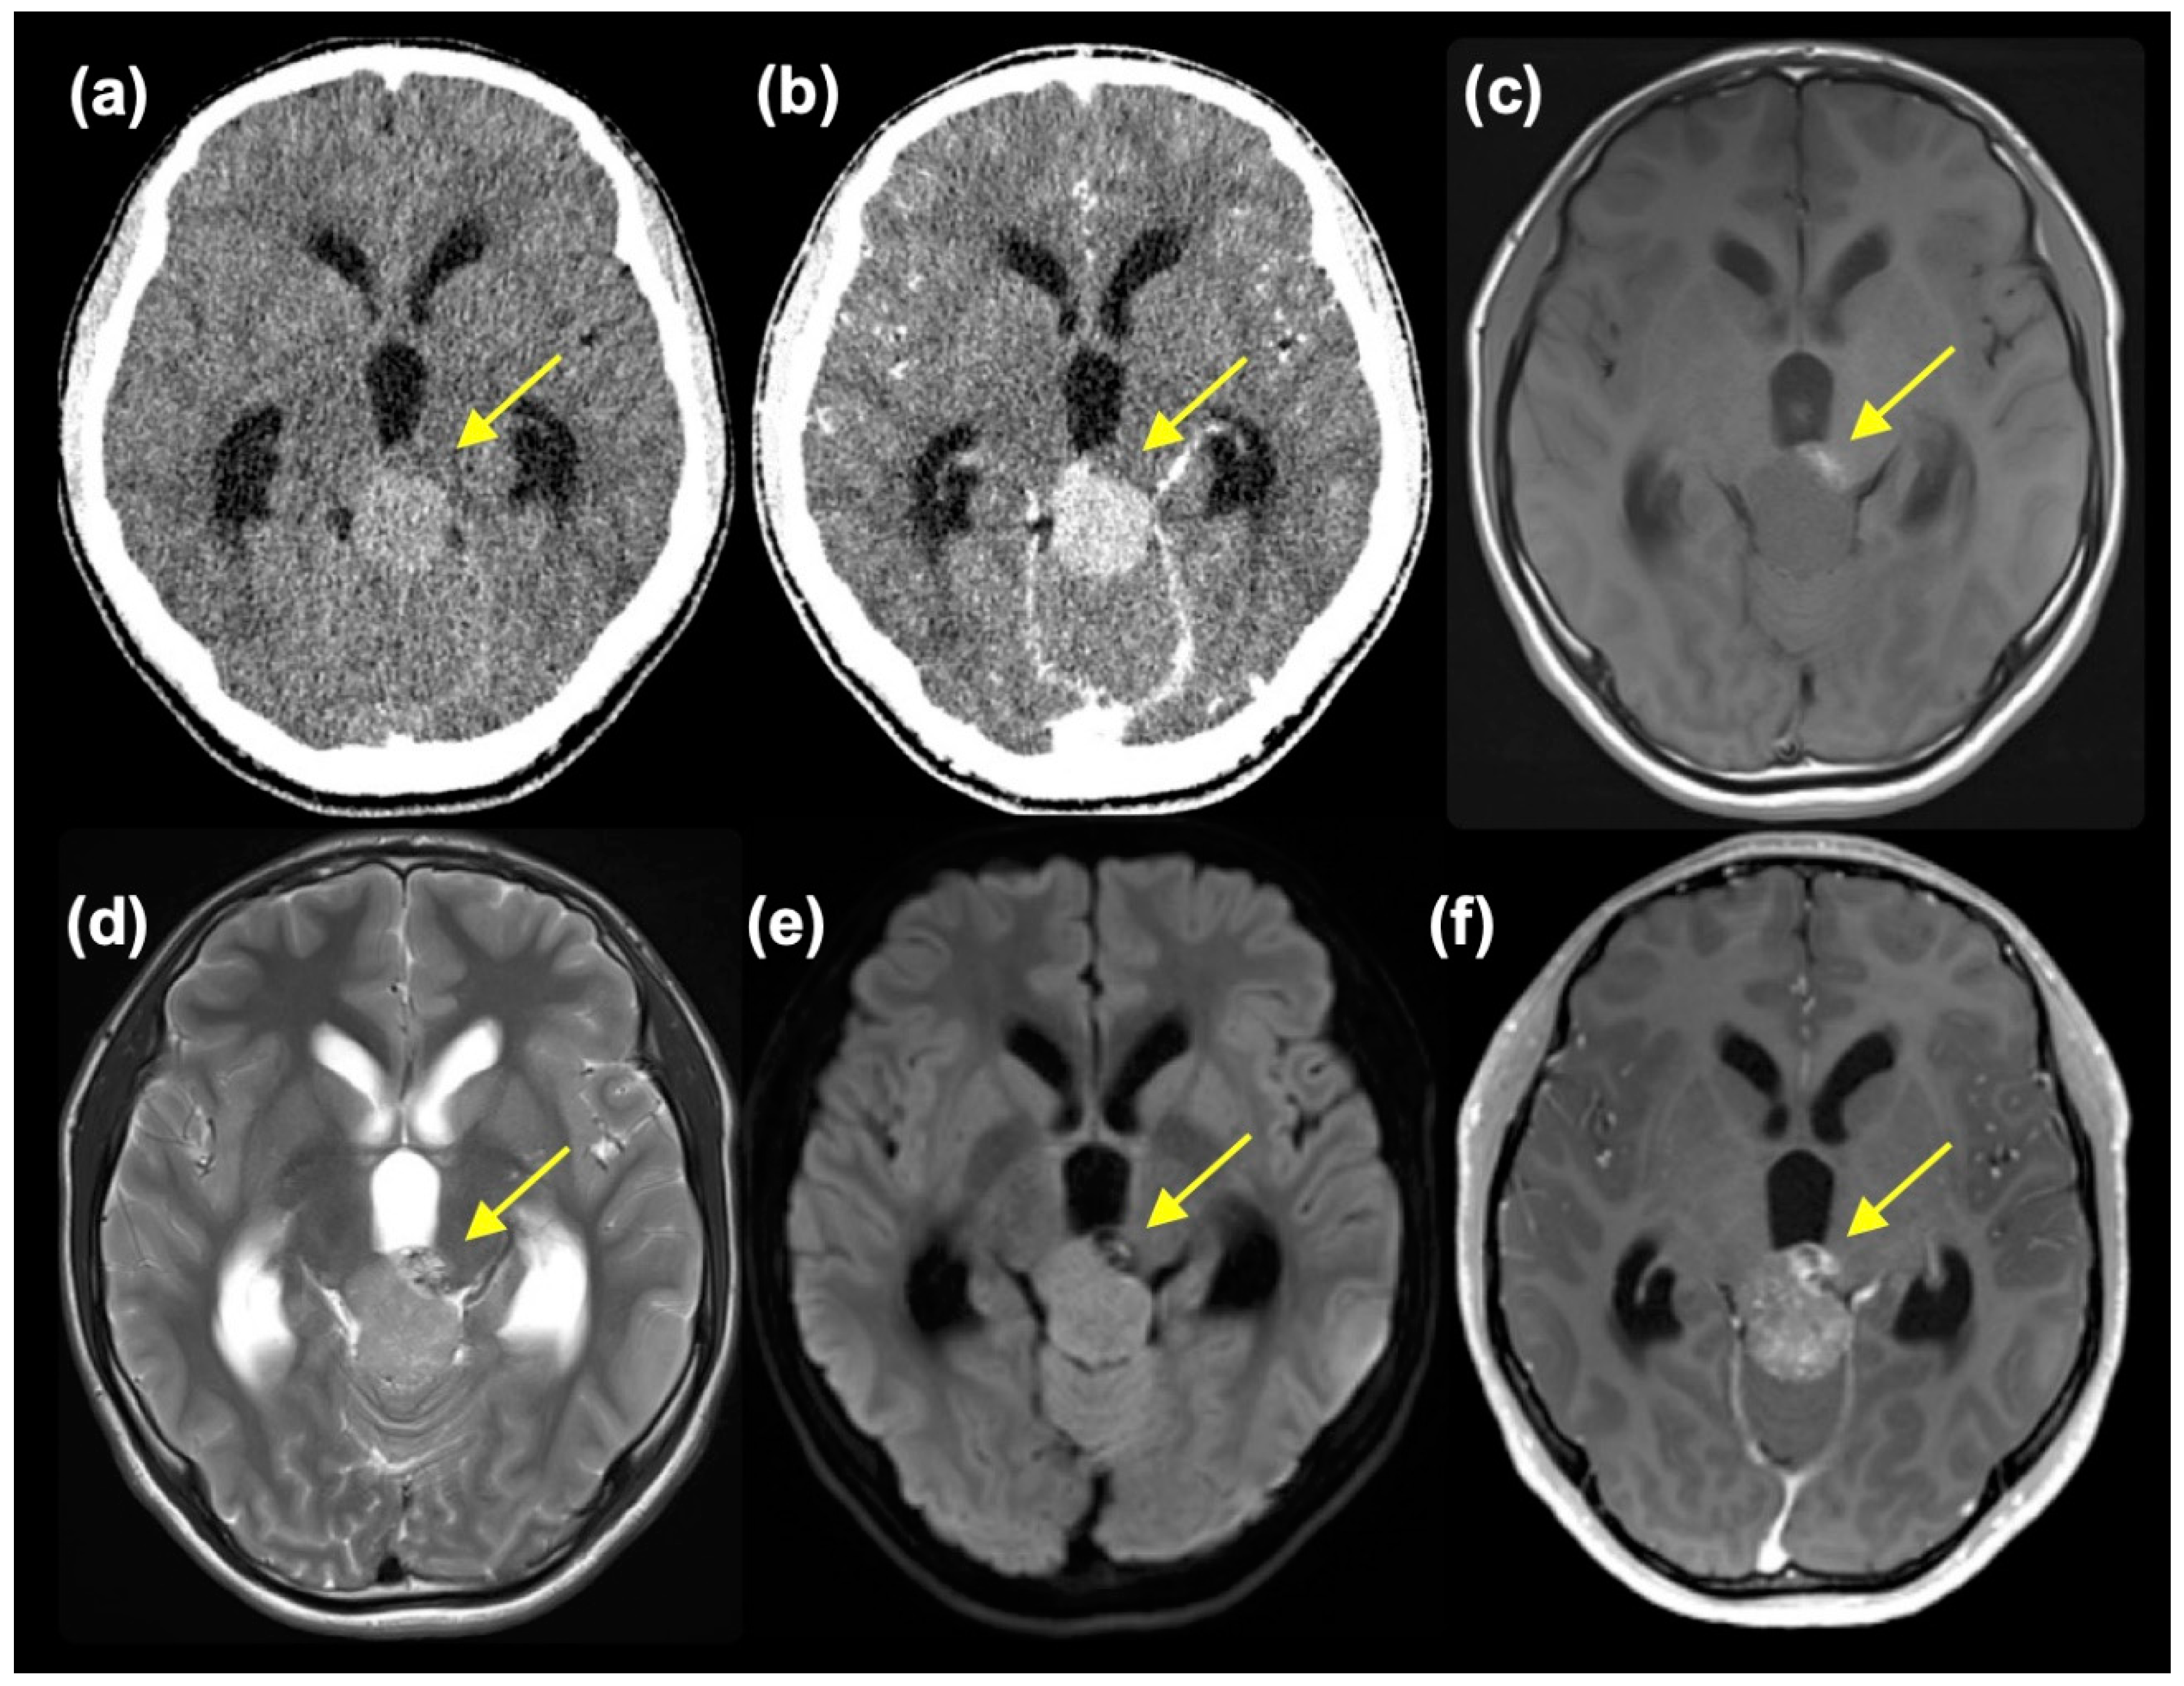

A 14-year-old boy without a notable history presented with worsening headaches, blurry vision, and vomiting. An MR scan taken at a neurosurgery clinic revealed a mass at the pineal region and accompanying obstructive hydrocephalus. He was referred to the Department of Neurosurgery, Niigata University, for further evaluation and treatment. At the initial presentation, he had a severe headache, and mild impairment of consciousness was observed (Glasgow Coma Scale 15 E4V5M6, but with mild disorientation). Extraocular movement was objectively normal, but the patient complained of blurry vision. No other neurological symptoms were observed. A head CT scan showed a slightly high-dense tumor mass, approximately 3.3 cm in diameter, at the pineal region with marked enlargement of bilateral lateral and third ventricles (Figure 1(a)). The tumor showed homogeneous enhancement, except for a small area at the left anterior part of the tumor, which was isodense on pre-contrast CT and did not enhance (Figure 1(b)). MR images also depicted tumor regions with different intensities. The main part of the tumor was isointense on T1-weighted images (T1WI) and slightly hyperintense on T2-weighted (T2WI) and diffusion-weighted images (DWI) with moderate enhancement. In retrospect, these intensities were thought to reflect calcification, although plain CT was not high dense. On the other hand, the left anterior portion of the tumor was hyperintense on T1WI, mixed hyper- and hypointense on T2WI, hypointense on DWI and showed heterogeneous enhancement (Figure 1(c)-(f)). A mixed type of germ cell tumor was suspected. However, at presentation, serum tumor markers were negative (AFP 5 ng/ml and β-HCG 6 mIU/ml).

Figure 1. Pre-contrast (a) and post-contrast CT and T1WI (c), T2WI (d), DWI (e), and post-contrast MRI showing two components (small component indicated with yellow arrow).